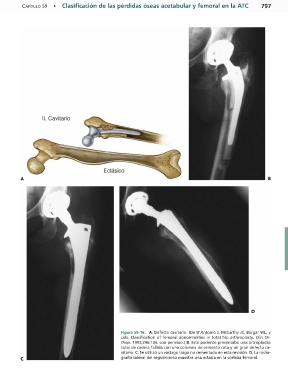

Figura 59-16.mA. Defecto cavitario. (De D’Antonio J, McCarthy JC, Bargar WL, y

cols. Classification of femoral abnormalities in total hip arthroplasty. Clin Or-

thop. 1993;296:134, con permiso.) B. Este paciente presentaba una artroplastia

total de cadera fallida con una columna de cemento rota y un gran defecto ca-

vitario. C. Se utilizó un vástago largo no cementado en esta revisión. D. La radio-

grafía lateral del seguimiento muestra una ectasia en la corteza femoral.